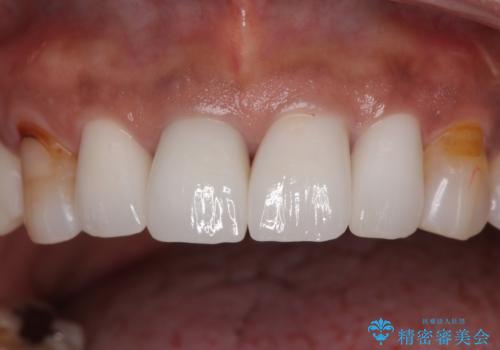

6本同時に処置を行うと、矮小歯をより大きく見えるように工夫ができるというメリットがありましたが、4本のみの処置でも十分に満足をされていらっしゃいました。

見た目も大事だが、なるべく削りたくないとのことで、取り急ぎ4本を補綴治療し、今後犬歯の色などが気になることがあれば、追って対応することとしました。